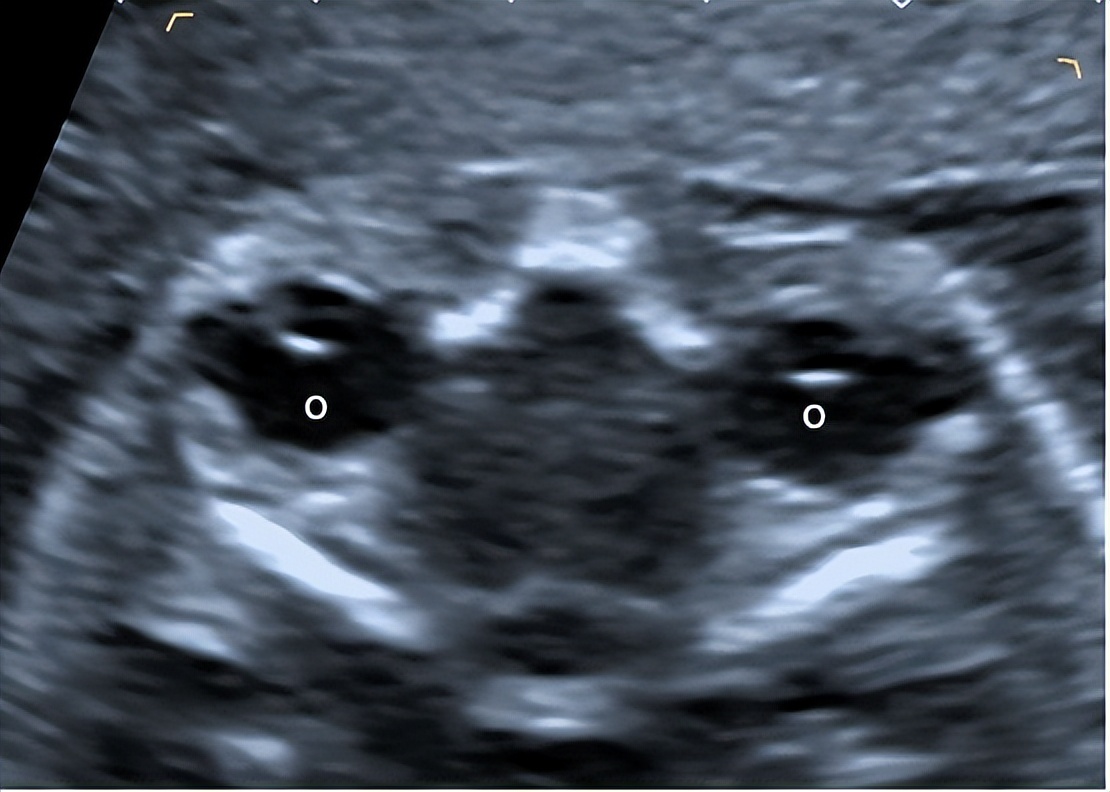

近期1.双眼球横切面

切面要求:同一平面上显示最大径线的双侧眼球(图1)。

观察内容:双侧眼球呈近圆形无回声,左右基本对称。

图1 孕23周双侧眼球横切面 显示双侧眼球(O:眼球)